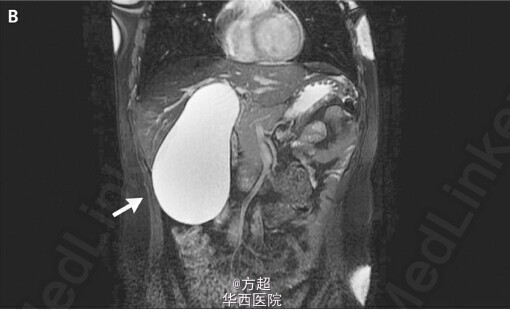

31岁青年女性,因间断发作右上腹疼痛就诊,自诉可于右侧腹部扪及缓慢长大包块;自诉无黄疸、发热、体重下降等情况,肝酶等实验室检查无异常,腹部超声未见异常,腹部MRI提示胆囊扩张17*8cm(如图A、B),但是并未发现胆管结石,胆管外源性受压以及胆管畸形;告知风险后予以腹腔镜下胆囊切除术,术中证实胆囊扩张积水,余无异常发现;术后患者症状逐步缓解。André Brito Queiroz, M.D., and Jocielle Santos de Miranda, M.D.N Engl J Med 2011; 364:e43;原文链接:http://www.nejm.org/doi/full/10.1056/NEJMicm1000943